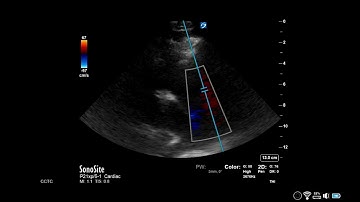

Estimation of RVSP